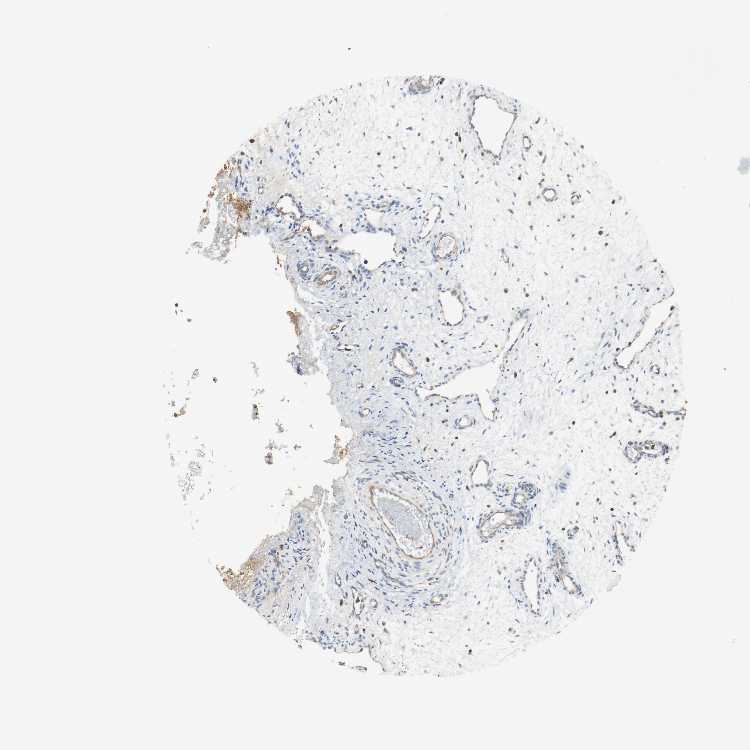

NASOPHARYNX - Antibody stainingi

Antibody staining in the annotated cell types in the current human tissue is reported as not detected, low, medium, or high, based on conventional immunohistochemistry profiling in selected tissues. This score is based on the combination of the staining intensity and fraction of stained cells.

Each image is clickable and will lead to virtual microscopy that enables deeper exploration of all samples and also displays staining intensity scores, fraction scores and subcellular localization as well as patient and tissue information for each sample.

Antibody HPA004832

Respiratory epithelial cells Low